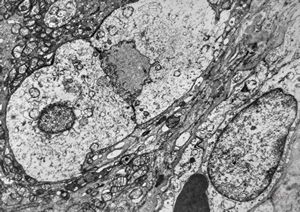

F,50y. | progressive multifocal leukoencephalopathy- viral particles in a glial cell

F,50y. | progressive multifocal leukoencephalopathy- viral particles in a glial cell

F,50y. | progressive multifocal leukoencephalopathy- viral particles in a glial cell